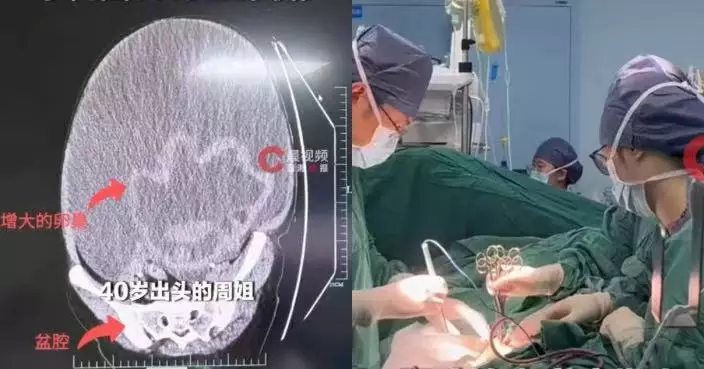

高齡手術風險大 醫生判斷為脂肪肉瘤

由於馮大爺年事已高,手術過程可能面臨大出血、器官功能衰竭等風險,因此此前多間醫院均認為風險過高,未有為他進行手術。家人之後帶他到空軍軍醫大學唐都醫院骨科就診,醫生經檢查後判斷,肩部巨大腫物為「脂肪肉瘤」。

2小時手術完整切除 多年負重終於解除

唐都醫院骨科團隊隨即為馮大爺制定手術方案,經過約2小時手術,醫生成功將這個幾乎包圍上臂四分之三的巨大腫瘤完整切除,並在手術過程中盡量避開重要血管及神經。手術後,馮大爺肩頭多年的負重終於解除,恢復情況良好。